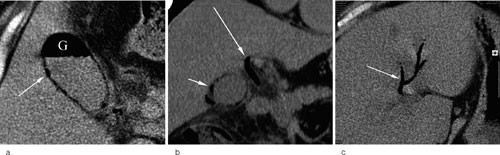

CT abdomen utført to dager etter innleggelsen viste gass i 1/3 av galleblærens lumen samt i ductus hepaticus communis og i intrahepatiske galleganger. Det var også gass i galleblæreveggen, men ikke i peribiliært vev (fig 1a-c). Det var ingen tegn til tumor. Behandling med cefuroksim samt metronidazol ble startet.

Differensialdiagnoser ved funn av gass i galleveier omfatter emfysematøs kolecystitt, en følgetilstand av papillotomi eller stentinnleggelse i galleveiene, enterobiliær fistel på grunn av gallesteinsperforasjon eller ekstrahepatisk biliært karsinom med enterisk penetrasjon, intraabdominal abscess, leverabscess og biliær lipomatose (1). Den mest sannsynlige diagnosen hos vår pasient var nå akutt emfysematøs kolecystitt.

Ved røntgen oversikt abdomen kan man se gass og væskespeil i galleblæren, men ofte feiltolkes dette som gass i duodenum. Det røntgenologiske bildet beskrives i tre stadier, som lettest erkjennes ved CT. I første stadium finnes gass i galleblæren, i andre stadium i tillegg gass i galleblæreveggen og i tredje stadium gass i omkringliggende vev (5, 6). Ultralydundersøkelse er den vanligst benyttede metoden ved mistanke om galleblæresykdom. Ved emfysematøs kolecystitt med lite gass i galleblæren kan ultralyd vise en ekkogen linje med «puddersnø»-ekko, og galleblærens begrensning kan visualiseres. Ved emfysematøs kolecystitt med mye gass kan man se et bredt takket ekkogent bånd med «puddersnø»-ekko og skygge bak. Galleblæreveggen kan ikke visualiseres, og diagnostikk er vanskelig. Ultralyd kan ikke differensiere mellom gass i galleblæreveggen eller omkringliggende vev. Gass i dypere galleveier kan ses ved ultralyd, og funn av dette indiserer mer fremskreden sykdom med mer alvorlig prognose (8). CT er den mest egnede undersøkelsen ved emfysematøs kolecystitt. Ved manglende visualisering av galleblæren, funn som beskrevet, spesielt hos eldre mannlige pasienter med kardiovaskulær sykdom, diabetes mellitus eller andre småkarsykdommer, bør man mistenke emfysematøs kolecystitt og dermed utføre CT.